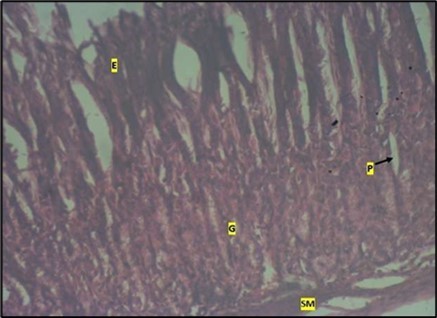

Histological examination of the stomach in control animals showed normal appearance of epithelial cells lining the mucosa and normal smooth muscles in the submucosa (Figure 8). However, administration of Abelmoschus esculentus at low dose showed deep epithelial gastric area with marked depletion of pits and goblet cells (circled area) and normal smooth muscles in the submucosa (Figure 9) and the high dose group showed dysplasia of gastric pits with goblet cells in the mucosa and the smooth muscles in the submucosa were mildly eroded (Figure 10).

Figure 8.control plate showing gastric pits with goblets cells (g). Smooth muscle layer (SM) and surface epithelium (e) appears normal. (H&E).

Figure 10.Image of a wistar rats stomach treated with high dose of abelmoschus esculentus showing dysplasia of gastric pits with the arrows mark (p). Goblet cells mark with arrow (g) appear at the basal mucosa and smooth muscle (sm) appear mildly eroded. The slide was stained using h & e technique. X100